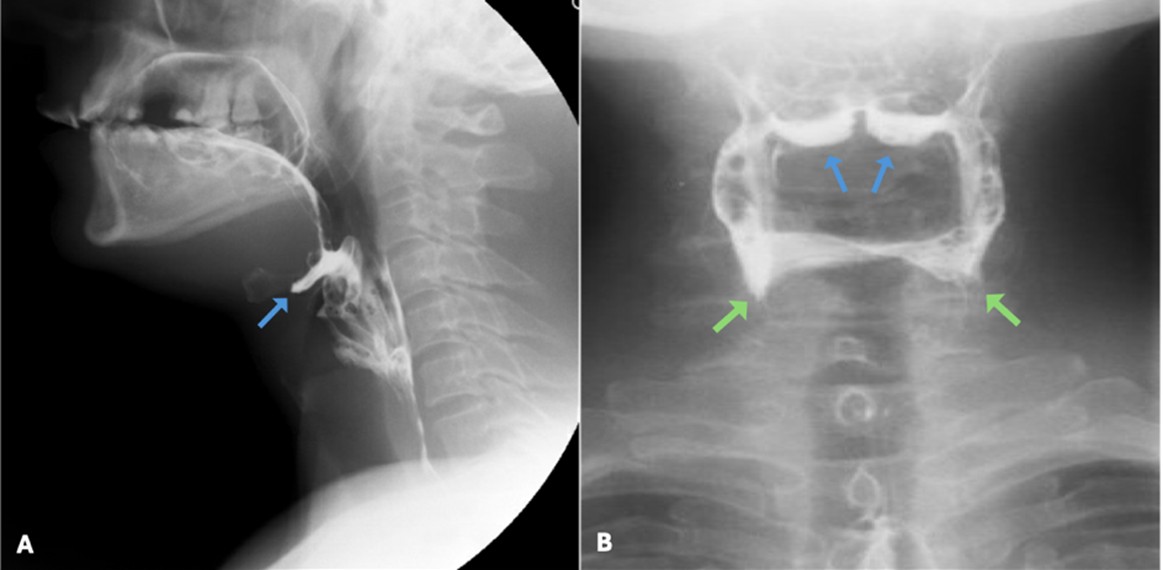

Pharyngeal peristalsis is achieved through sequential contraction of the pharyngeal constrictors, which propel the boluses forward through the upper oesophageal sphincter and into the oesophagus. Normal pharyngeal transit times, defined as the time it takes for the bolus to move from the oropharynx to the oesophagus, are usually under one second. (Fig. 13)

Impaired pharyngeal muscular contraction results in increased pharyngeal transit times and persistence of pharyngeal residues in the piriform sinuses, posterior hypopharyngeal wall or above the upper oesophageal sphincter. Anterior-posterior views should be evaluated for asymmetric contraction of the pharyngeal muscles or asymmetric retention of contrast, findings which may suggest vagus nerve paresis or the presence of a mass, respectively. (Fig. 14)

Figure 14: Pharyngeal residues in the vallecula (blue arrows) and piriform sinuses (green arrows) in lateral (A) and anterior-posterior (B) views